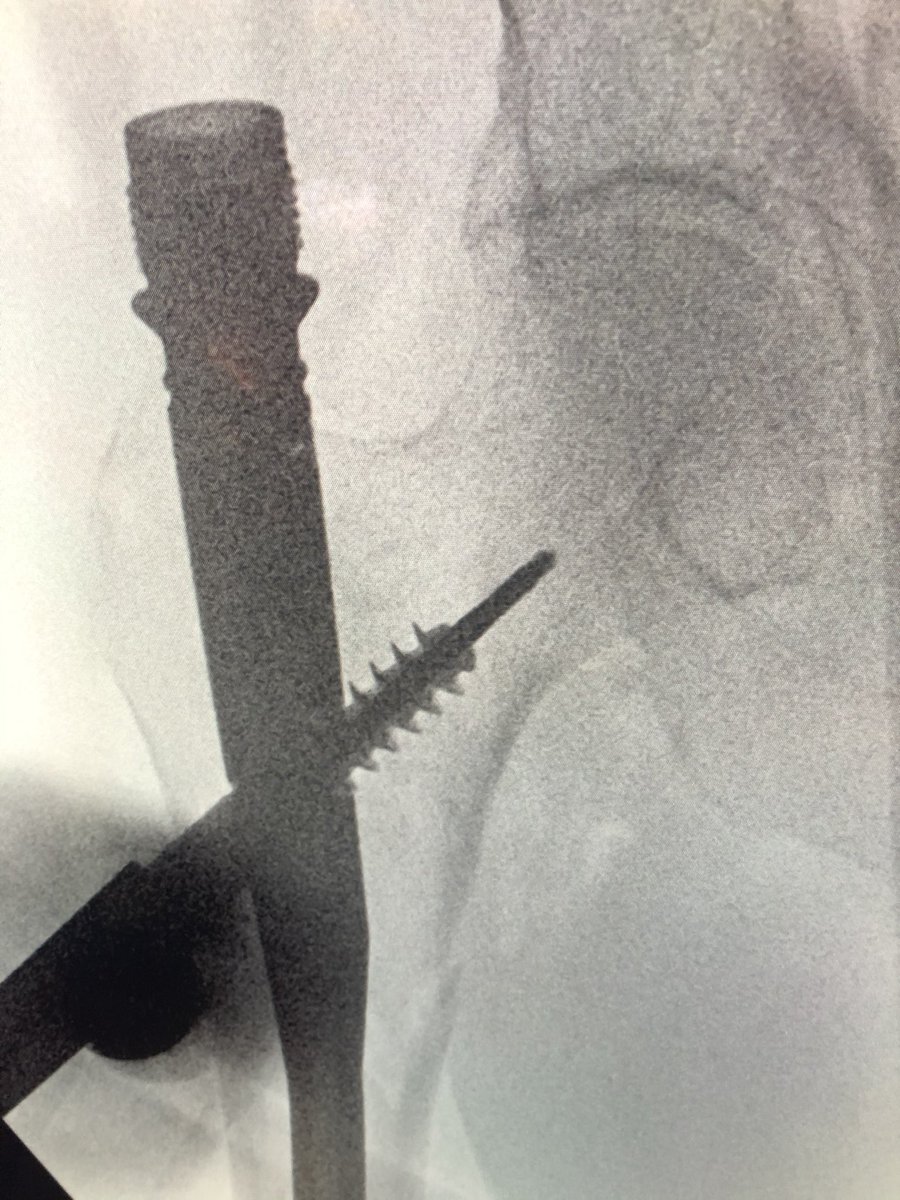

[1/2] Always make sure your wire stays where you put it. The original wire placement for drilling was this, but after drill came out so did the wire, and the screw was placed over the wire without ascertaining that it was back in proper position...

[2/2] This resulted in a completely different (anterior) trajectory of screw placement (left), which then had to be corrected (right). So always check.